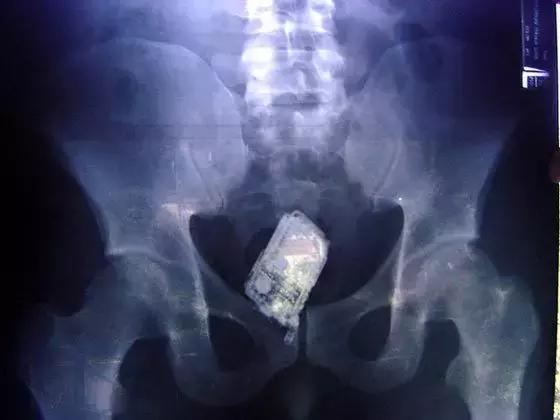

▲犯人私藏的手机

最后,是“看图识物”环节,请大家辨认下面三张图中的物体,欢迎在留言区发表你的看法哦。